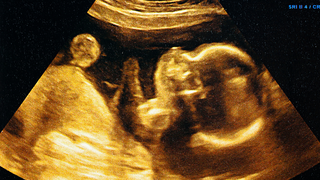

Abdominal pain is a common experience during pregnancy. Most of the time, it happens mainly because of implantation (when the fertilised egg attaches to the lining of your uterus). This can cause mild cramping or twinges in your lower belly. But it’s important to remember that in some cases, stomach pain might signal something more serious that needs urgent attention.

Abdominal pain during pregnancy can be confusing and even a little scary, but it’s something a lot of people experience. You might notice a sharp twinge around your ovaries, a dull ache, or even a constant, uncomfortable pressure in your lower belly.

As your pregnancy progresses, your uterus begins to stretch and grow to accommodate your developing baby. This growth means it starts pressing on nearby areas, including your ovaries and the ligaments that hold your uterus in place. These ligaments are connected to your pelvis and uterus, and as they stretch, you may feel a dull or achy sensation.